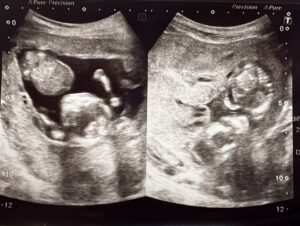

その羊水がほぼゼロと告げられたKさん(@keroppi__keroppi)の双子は、お腹の中で命をつなぎ、無事に誕生しました。

Kさんは妊娠7週で胎嚢と心拍を確認しました。次の健診を待つ間の9週で大量出血があり、診察の結果、原因は特定できないまま安静の指示を受けます。その際、初めて双子であることがわかりました。

その後も出血が続き「絨毛膜下血腫」と診断。週1回の通院を続ける中、13週のエコーで血腫は縮小していたものの、先に生まれる赤ちゃんの羊水がほぼない状態だと告げられました。

そこで「どうにかして羊水が増える方法がないだろうか、救える可能性がないか」と情報を求めて、義妹さんがエコー写真と共にTikTokに載せてくれたそうです。